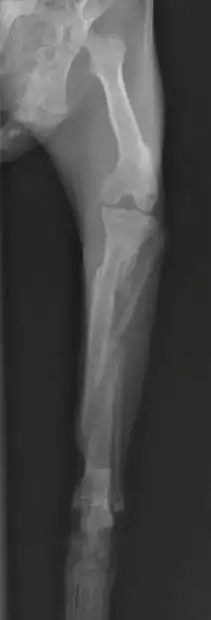

I did see a recent case which I think is quite relevant here. This is a young cat who fell off a third floor balcony, not once but twice over the course of a couple months. After the initial fall, he was limping but this seemed to resolve fairly quickly so the owner never brought him into a vet. A few months later, he had another fall, but did not seem to be getting better as quickly, and this is when I saw him. It was over a week after the second fall that he was brought in to me. These were his x-rays:

Similarly to your cat, this cat had fractures of his tibia and fibula. There are two primary fractures on the tibia. The more distal (lower) fracture shows some periosteal proliferation and callus formation, which is what happens when the body tries to heal a fracture. This is the hazy area between the fracture segments. I suspect that this is the original fracture from a couple months ago. The more proximal fracture appears more recent with no callus formation.

On his exam, the fracture did appear very stable, meaning I was unable to move the individual fracture fragments much. The cat was partially weight-bearing by this point.

I sent this cat to an orthopaedic surgeon for a second opinion and they advised to hold off on surgery for this cat, as the fractures were stable and minimally displaced. Although the x-ray looks terrible, with rest and pain management we are hopeful that this one will heal on its own. Time will tell, hoping to have a progress check on this cat in a few weeks.